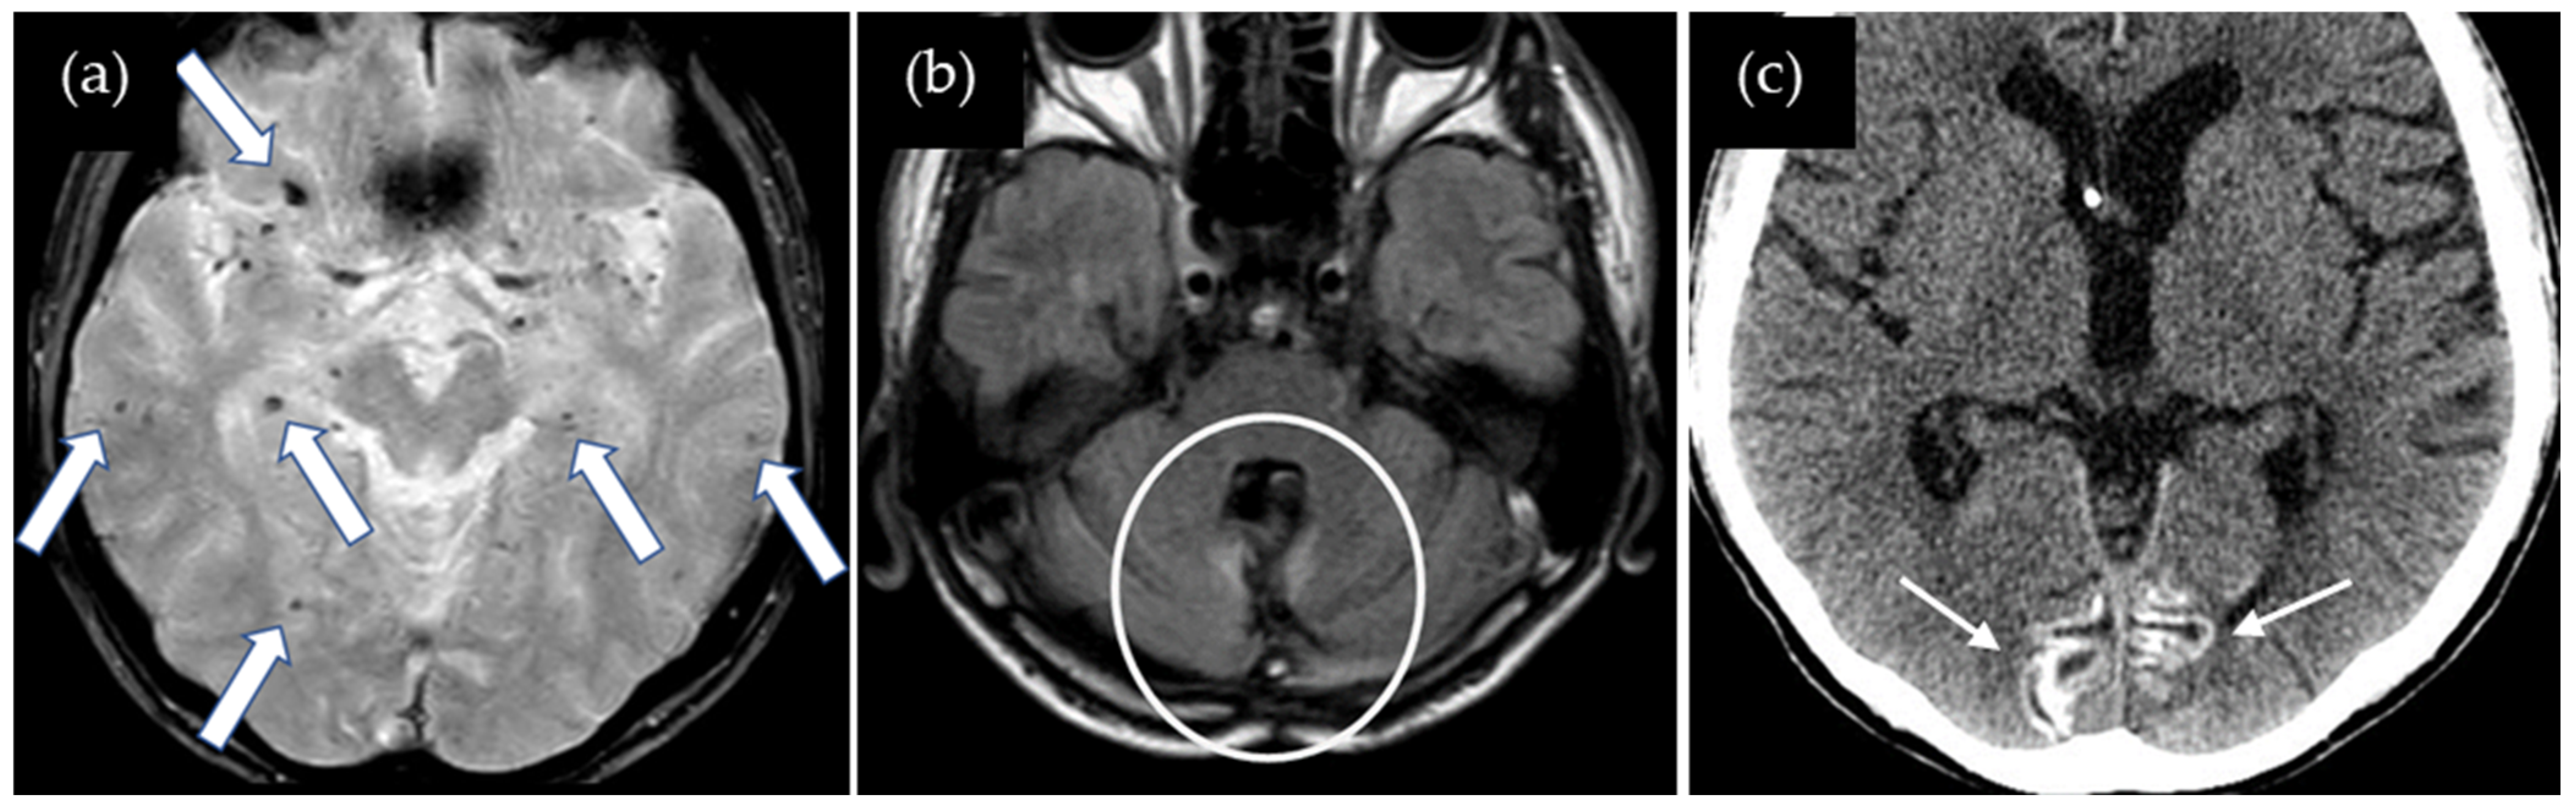

A 38-year-old man was found collapsed on the stairs and subsequently admitted to our hospital. On admission, right upper and lower extremity paresis was noted. He underwent left parietal craniotomy for a traumatic head injury at the age of six months. Cadaveric dura mater use was not confirmed. He had no history of hypertension or familial CAA. CT showed a lobar ICH in the left parietal lobe, and SWI showed multiple cortical CMBs adjacent to the ICH (Figure 2). The CAA-SVD score was 2 based on the previous literature [5], consisting of two points for lobar CMBs, zero points for cSS, zero points for CSO-PVSs, and zero points for WMH. Neither CSF examination nor amyloid PET was performed. Thus, this case was considered a possible iCAA based on the criteria [1].

Figure 2.

SWI shows multiple CMBs (arrows) adjacent to the lobar hemorrhage in the left parietal lobe (square).

A 47-year-old man presented with dysarthria and transient symptoms of weakness and numbness in the left upper extremity. He had a history of a cerebellar tumor that had been removed at the age of 11 years. Use of cadaveric dura mater, Lyodura, was confirmed, although any other detailed information about surgical procedure was not available. Radiation therapy was not performed. He had no history of hypertension or familial CAA. T2*-weighted images showed no cSS in the right precentral gyrus or other gyri, while multiple lobar CMBs were detected mainly in both cerebral hemispheres, with several CMBs also observed in the cerebellum (Figure 3). The CAA-SVD score was 2 based on the previous literature [5], consisting of two points for lobar CMBs, zero points for cSS, zero points for CSO-PVSs, and zero points for WMH. CT showed prominent cortical calcifications in both occipital lobes, which were not visible on the T2*-weighted image. Neither CSF examination nor amyloid PET was performed. Thus, this case was considered a possible iCAA based on the criteria [1].

Figure 3.

(a) T2*-weighted image shows no cSS in the right precentral gyrus or other gyri, while multiple lobar CMBs (arrows) are detected in both cerebral hemispheres; (b) 2D FLAIR shows postoperative changes in the cerebellum (circle); (c) CT shows prominent cortical calcifications in both occipital lobes (small arrows).